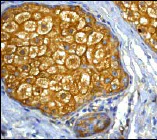

This data was generated using the same anti-NF-kB p65 antibody clone, E379, in a different buffer formulation (ab32536).

Immunohistochemical analysis of paraffin-embedded Human prostatic hyperplasia tissue labeling NF-kB p65 with ab32536 at 1/5000 (0.098 ug/ml) dilution followed by a ready to use LeicaDS9800 (Bond™ Polymer Refine Detection). Cytoplasmic staining on human prostatic hyperplasia. The section was incubated with ab32536 for 30 mins at room temperature. The immunostaining was performed on a Leica Biosystems BOND® RX instrument. Counterstained with Hematoxylin.

Secondary antibody only control : Secondary antibody is a ready to use LeicaDS9800 (Bond™ Polymer Refine Detection).

Heat mediated antigen retrieval with Citrate buffer (pH 6.0, epitope retrieval solution 1) for 20 mins